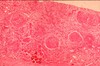

What is seen in H&E stains of acute proliferative glomerulonephritis?

- neutrophils plugging up glomerular lumens

- cells have multi-lobed nuclei

- cannot distinguish epithelial from mesangial from endothelial etc.

- marked hypercellularity (many black dots)

- structural loss